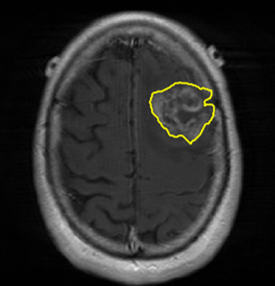

We argue that the sub-optimal paradigm of processing different abstractions within a single CNN pipeline can be remedied through the effective processing of information in a structured manner. Consequently, we devise strategies for disentangling the edge and texture information within a single training pipeline. Figure 2 illustrates how our proposed module, dubbed EG-CNN, can be paired with any existing CNN encoder-decoder to improve segmentation quality near intensity edges. We have applied our EG-CNN to the tasks of brain and liver tumor segmentation in medical images (Figure 3).

Edge-Aware 2D Image Segmentation Networks

[49; 48]: Fully convolutional neural networks (CNNs) have proven to be effective at representing and classifying textural information, thus transforming image intensity into output class masks that achieve semantic image segmentation. In medical image analysis, however, expert manual segmentation often relies on the boundaries of anatomical structures of interest. We propose 2D edge-aware CNNs for medical image segmentation. Our networks are designed to account for organ boundary information, both by providing a special network edge branch and edge-aware loss terms, and they are trainable end-to-end. We validate their effectiveness on the task of brain tumor segmentation using the BraTS 2018 dataset. Our experiments reveal that our approach yields more accurate segmentation results, which makes it promising for more extensive application to medical image segmentation. -

Plug-and-Play Edge-gated 3D Image Segmentation Networks

[50]: We propose a plug-and-play module, dubbed Edge-Gated CNNs (EG-CNNs), that can be used with existing encoder-decoder architectures to process both edge and texture information. The EG-CNN learns to emphasize the edges in the encoder, to predict crisp boundaries by an auxiliary edge supervision, and to fuse its output with the original CNN output. We evaluate the effectiveness of the EG-CNN against various mainstream CNNs on the publicly available BraTS19 dataset for brain tumor semantic segmentation, and demonstrate how the addition of EG-CNN consistently improves segmentation accuracy and generalization performance. -